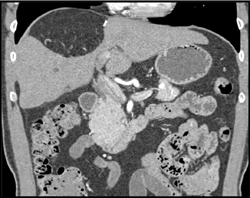

Diagnosis

1cm Hepatocellular Carcinoma (HCC)